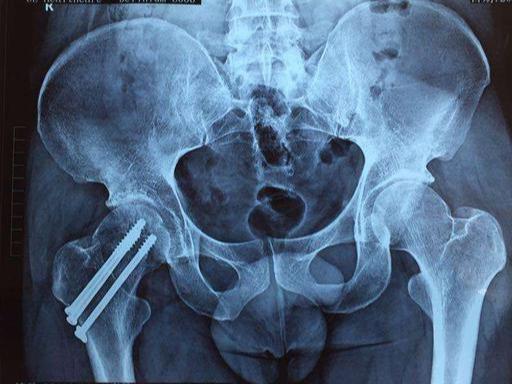

这些并发症的存在,所以髋部骨折,以前被叫做“临终性骨折”或者“人生的最后一次骨折”。腰椎骨折和下肢的其他骨折影响小一点。但急性损伤的伤害,对身体的打击,脂肪栓塞,出血等等,也是很严重的,老人家的身体恢复能力不够强,很多就一蹶不振了。加上没有科学的护理,导致很多老人家熬不过这一关。就算熬过了这一关,身体状况也大打折扣,后面发生其他并发症的可能性也大了很多。寿命受到影响也很正常!!

现代骨科的发展和护理水平的提高,老百姓经济水平的上升,交通的便利,大家观念的改变,让很多老人得到及时的救治,挽救了无数的老人。特别是人工关节和微创技术的日新月异,快速康复理念的普及,更是骨折老人的福音。通过手术治疗,绝大多数老人得到康复,不过,个别还是还是出现了并发症,导致无法康复或者死亡,只是几率比以前已经大大的降低了,相信随着医疗护理水平的提升,会有越来越多的老人得到正确的治疗。